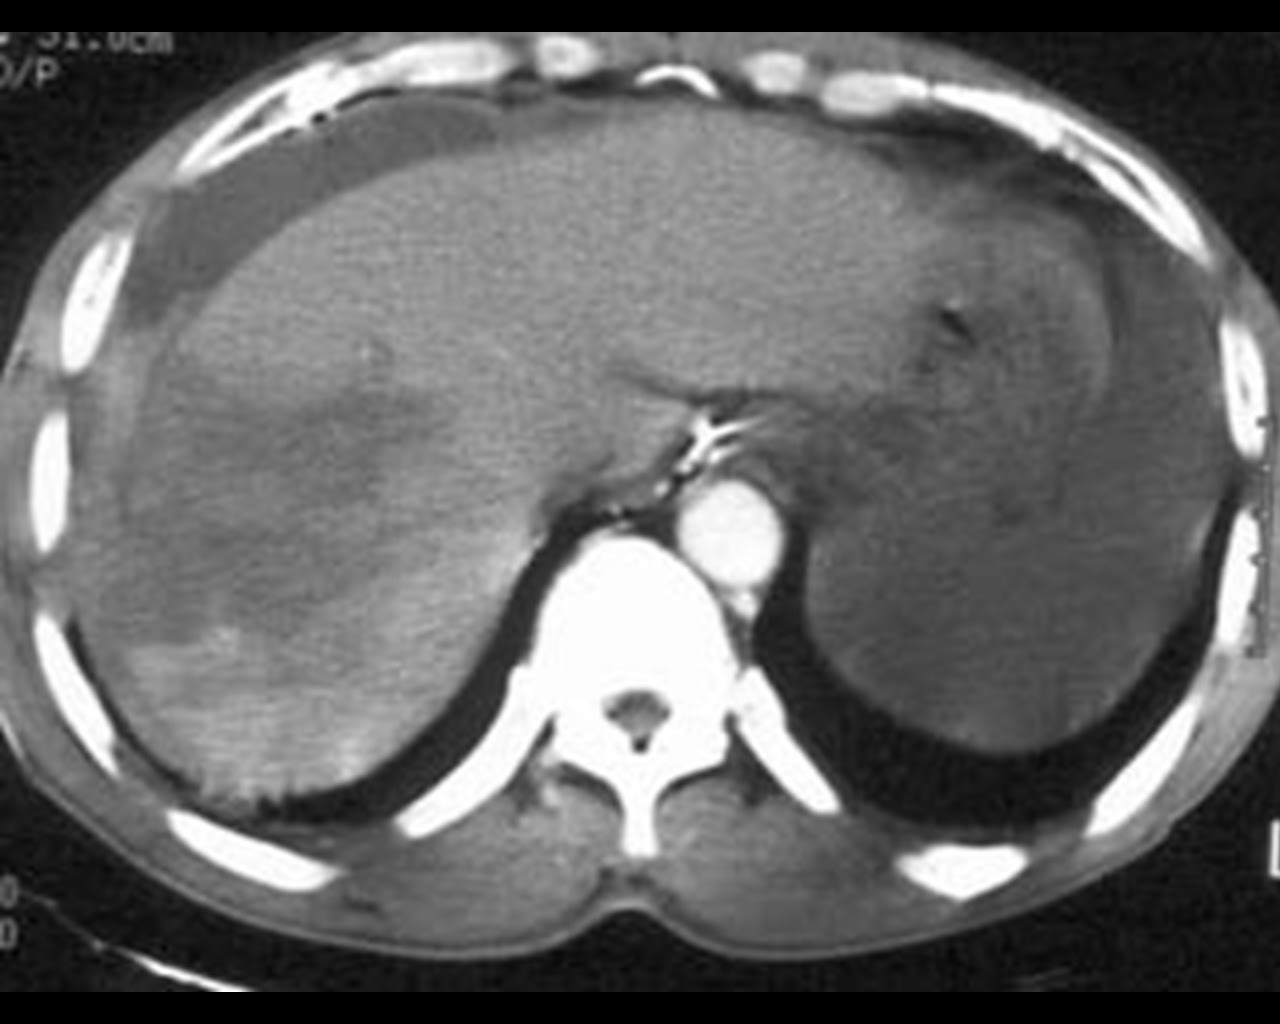

I’ve never quite been sure of the derivation of the phrase. A perfect example of its use is in a slide such as this.

There is simply so much “going on” in this image that the audience will be unable to derive meaning from any of the images (or worse still from the speech) because they are trying to decide which image to actually look at. Help the audience and simply project each image as required. (It’s a Grade IV Liver laceration)